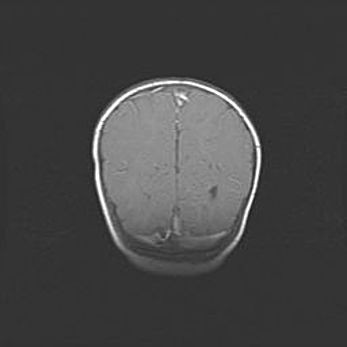

Открытая гидроцефалия.

Возраст: 9 месяцев 12 дней

Вес: 6800 г

Пол: мужской

Окружность головы: 41,5 см

Срок гестации: 28 недель

Гидроцефалия головного мозга у новорожденных имеет характерный признак: опережающий рост окружности головы приводит к визуально хорошо определяемой гидроцефальной форме сильно увеличенного в объёме черепа. Детские неврологи определяют следующие симптомы гидроцефалии у грудничков: выбухающий напряжённый родничок, частое запрокидывание головы, смещение глазных яблок к низу.